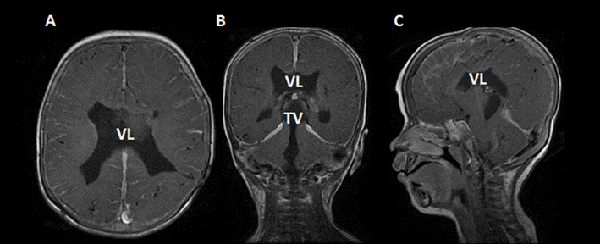

Reingreso a los 26 días postquirúrgicos con fiebre, irritabilidad, llanto persistente, rechazo al alimento; y signos de hipertensión endocraneana. Se tomó muestra de líquido cefalorraquídeo (LCR), en el cual se aíslo Enterobacter complex (E. hormaechei), se realizó resonancia magnética de cerebro con contraste, donde se evidenció realce a nivel ependimario compatible con ependimitis (Figura 1). Se colocó DVE y realizó un nuevo tratamiento con meropenem y colistin endovenoso asociado a tratamiento intraventricular con colistin. La dosis de colistin fue ajustada en base a el cálculo por imágenes del volumen ventricular. Se administró una dosis diaria de 4 mg de colistin, con posterior lavado de la guía con 1 ml de solución fisiológica. Durante la internación se realizaron 4 procedimientos endoscópicos que consistieron en lavados ventriculares, aspiración del contenido purulento intraventricular, acueductoplastia con colocación de catéter de DVE entre el tercer y el cuarto ventrículo (tras constatar re obstrucción del acueducto) con el objetivo de mantener la permeabilidad de la misma y de esta manera asegurar la llegada de antibiótico intraventricular al cuarto ventrículo. Se tomaron muestras del LCR cada 72-96 horas, utilizado como referencia de evolución las características citofisicoquímicas, el valor de ácido láctico y los cultivos. Luego de 21 días de tratamiento antibiótico, la paciente mejoró clínicamente y los parámetros infecciosos de LCR se normalizaron. Se retiró el catéter trans acueductal bajo visión directa por endoscopia y en el mismo procedimiento tras observar oclusión del ostoma previo, se repitió el procedimiento de TVE que no fue exitoso, por lo que se colocó una DVP presión fija media. No se registraron complicaciones asociadas en los procedimientos endoscópicos.

Figura 1: RM de encéfalo prequirúrgica: A) corte axial, B) coronal y C) sagital, ponderado en T1 con contraste. Se observa dilatación del sistema ventricular, ausencia de septum pellucidum, adelgazamiento de sustancia blanca periventricular y cuerpo calloso, con realce ependimario compatible con ventriculitis (flecha).